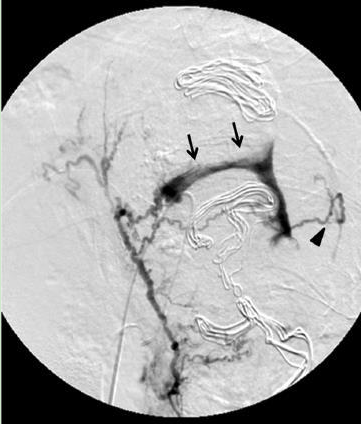

图 1. 箭头可见右侧子宫动脉内造影剂渗出,提示活动性出血,黑色箭头提示左侧动脉可见,提示出血也同时来自左侧